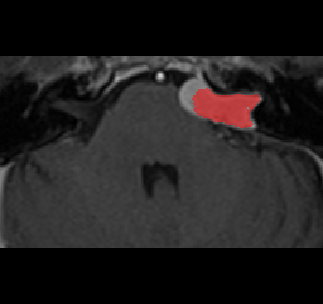

Recently, deep learning methods have achieved state-of-the-art performance in many medical image segmentation tasks. Many of these are based on convolutional neural networks (CNNs). For such methods, the encoder is the key part for global and local information extraction from input images; the extracted features are then passed to the decoder for predicting the segmentations. In contrast, several recent works show a superior performance with the use of transformers, which can better model long-range spatial dependencies and capture low-level details. However, transformer as sole encoder underperforms for some tasks where it cannot efficiently replace the convolution based encoder. In this paper, we propose a model with double encoders for 3D biomedical image segmentation. Our model is a U-shaped CNN augmented with an independent transformer encoder. We fuse the information from the convolutional encoder and the transformer, and pass it to the decoder to obtain the results. We evaluate our methods on three public datasets from three different challenges: BTCV, MoDA and Decathlon. Compared to the state-of-the-art models with and without transformers on each task, our proposed method obtains higher Dice scores across the board.